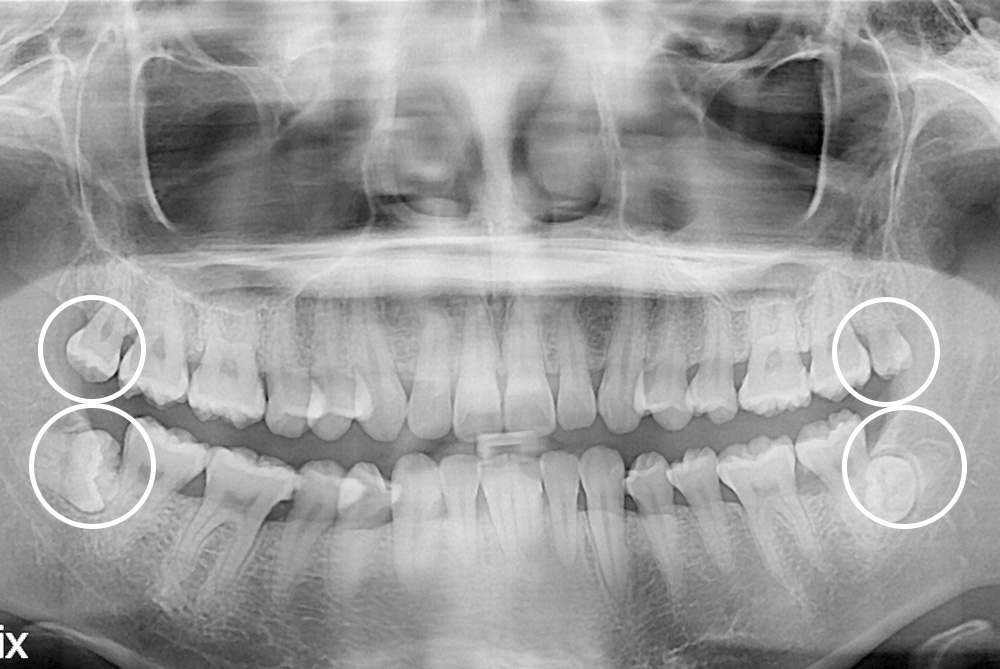

[사랑니] 매복 사랑니 발치

치료전 : 2021-09-21